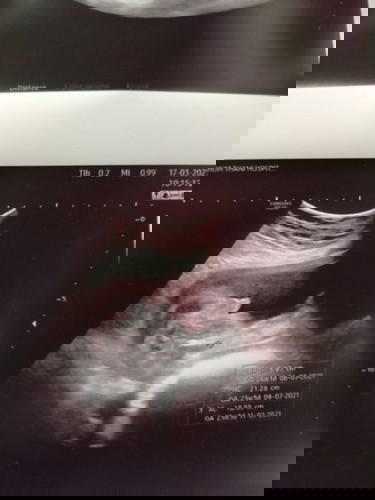

ตอนแรกแค่อยากรู้ว่าน้องครบสามสิบสองไหม หมอบอกว่าน้องแข็งแรงมาก และนางก็ถ่างขาให้เห็นว่านางเป็นผู้ชาย

ชัดมากเลยค่า😆😆